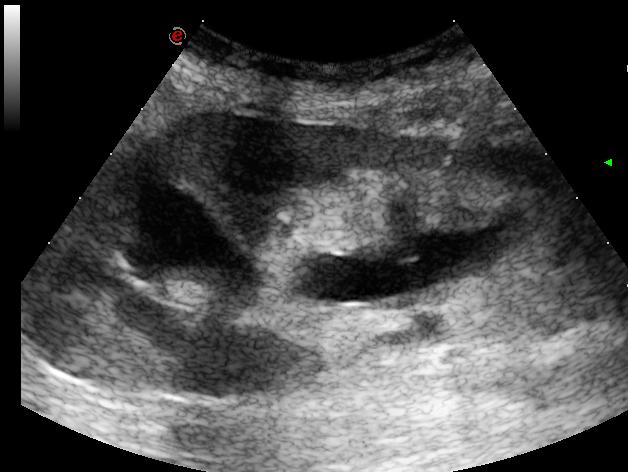

a vascularis resistentia a normál határon belül (RI: 0,72)

az ureter fala vaskos, oedemás és hypervascularisatiot mutat (ez okozza a pyelectasiát)

percutan nephrostoma készítés történt UH navigációval